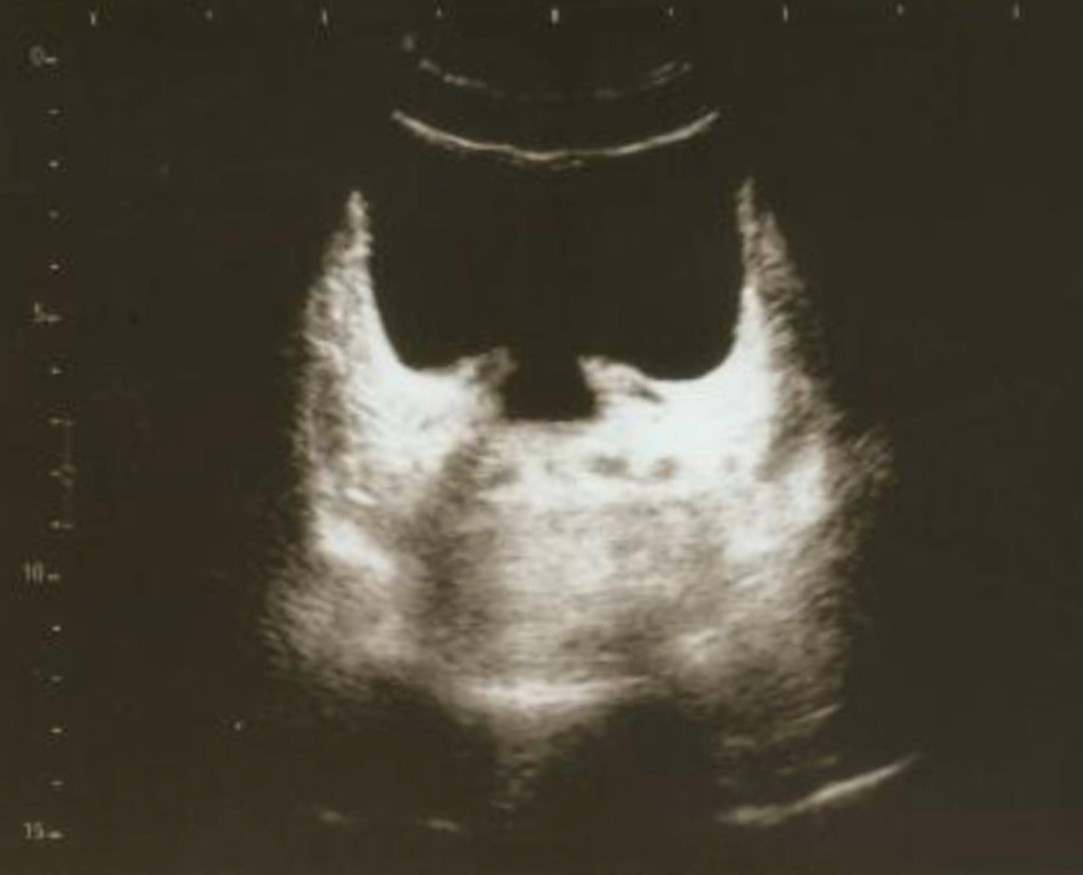

27 de febrero de 2025iTind ofrece excelentes resultados en el tratamiento de la hiperplasia benigna de próstataAdemás de preservar la función sexual y eyaculatoria y no provocar incontinencia urinaria, los resultados demuestran que se trata de una técnica senc...